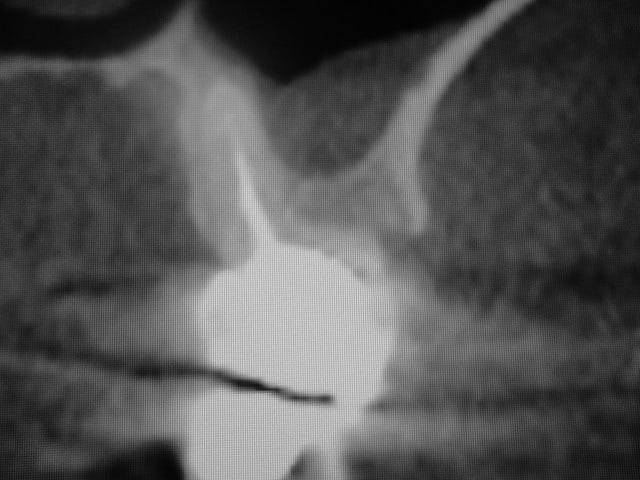

Bonsoir merci pour ta question, comme tu vois sur la radioDVT il n y avait pas assez de place pour mettre un 6,5mm seulement la racine palatinale était d une longueur de 10/12 mm. Mon premier challenge etait d avoir une premiere stabilité supérieure à 40 Ncm.Le laboratoire est donc important pour que le patient puisse nettoyer facilement la région implantaire.

la radioDVT que j ai oublié de poster